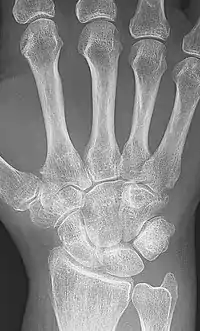

Ankylosis is a stiffness of a joint due to abnormal adhesion and rigidity of the bones of the joint, which may be the result of injury or disease. The rigidity may be complete or partial and may be due to inflammation of the tendinous or muscular structures outside the joint or of the tissues of the joint itself.[1]

When the structures outside the joint are affected, the term "false ankylosis" has been used in contradistinction to "true ankylosis", in which the disease is within the joint. When inflammation has caused the joint-ends of the bones to be fused together, the ankylosis is termed osseous or complete and is an instance of synostosis. Excision of a completely ankylotic shoulder or elbow may restore free mobility and usefulness to the limb. "Ankylosis" is also used as an anatomical term, bones being said to ankylose (or anchylose) when, from being originally distinct, they coalesce, or become so joined that no motion can take place between them.[1]